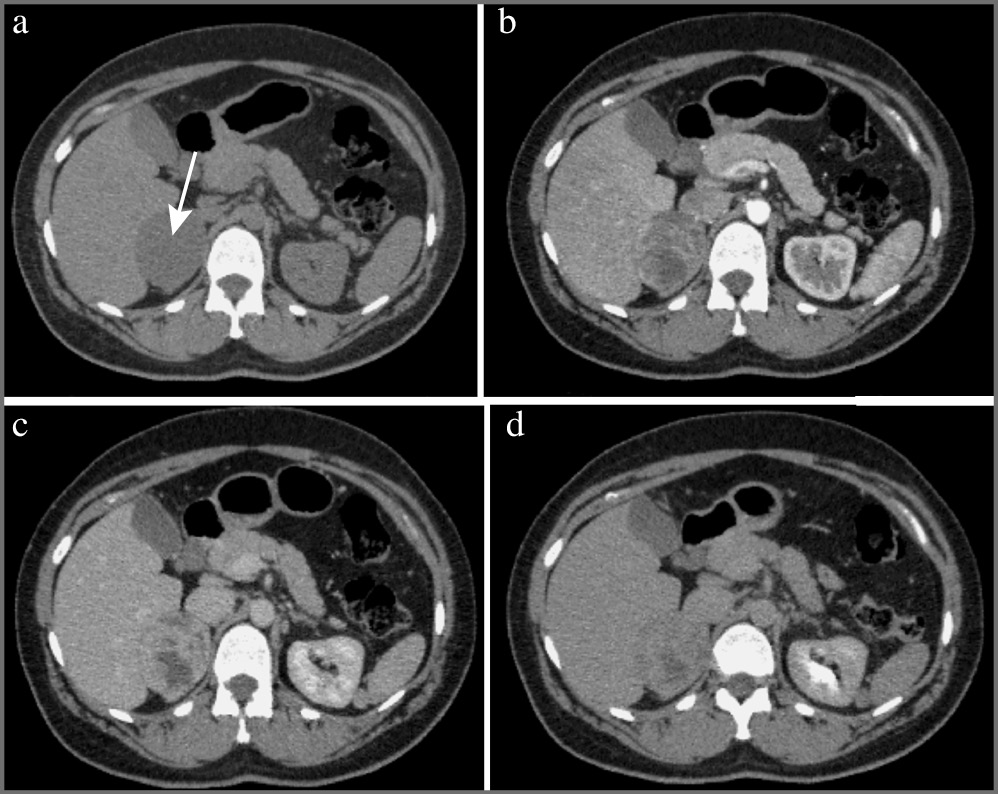

Феохромоцитома – опухоль, происходящая из хромаффинных клеток мозгового вещества надпочечников, и примерно в 90% случаев она секретирует катехоламины, что сопровождается повышенным уровнем метанефринов (метаболитов катехоламинов) в сыворотке крови и моче. Феохромоцитомы вненадпочечниковой локализации называются параганглиомами. КТ-картина феохромоцитом имеет разные признаки. Размер может варьировать от 1,2 до 15 см, в среднем около 5 см. Небольшие образования чаще однородны, в то время как более крупные обычно неоднородны с участками жидкостной плотности (зонами некроза), зонами кровоизлияний, внутренними перегородками, а также обызвествлениями. Большинство опухолей интенсивно накапливает контрастный препарат в артериальную фазу с последующим умеренным его вымыванием к отсроченной фазе. Контуры образования, как правило, четкие, ровные за счет наличия капсулы (рис. 3). В редких случаях феохромоцитомы могут в структуре иметь включения макроструктурного жира, что также характерно и для миелолипом [14].

Рис. 3. Феохромоцитома правого надпочечника (стрелка). МСКТ, аксиальная проекция: a – нативная фаза; b – артериальная фаза; c – венозная фаза; d – отсроченная фаза.

Следует отметить, что, несмотря на то, что выраженное вымывание контрастного препарата для феохромоцитом нехарактерно, в редких случаях они могут иметь характеристики вымывания, аналогичные аденомам (APW более 60% и RPW более 40%), что затрудняет установку диагноза [14, 15].